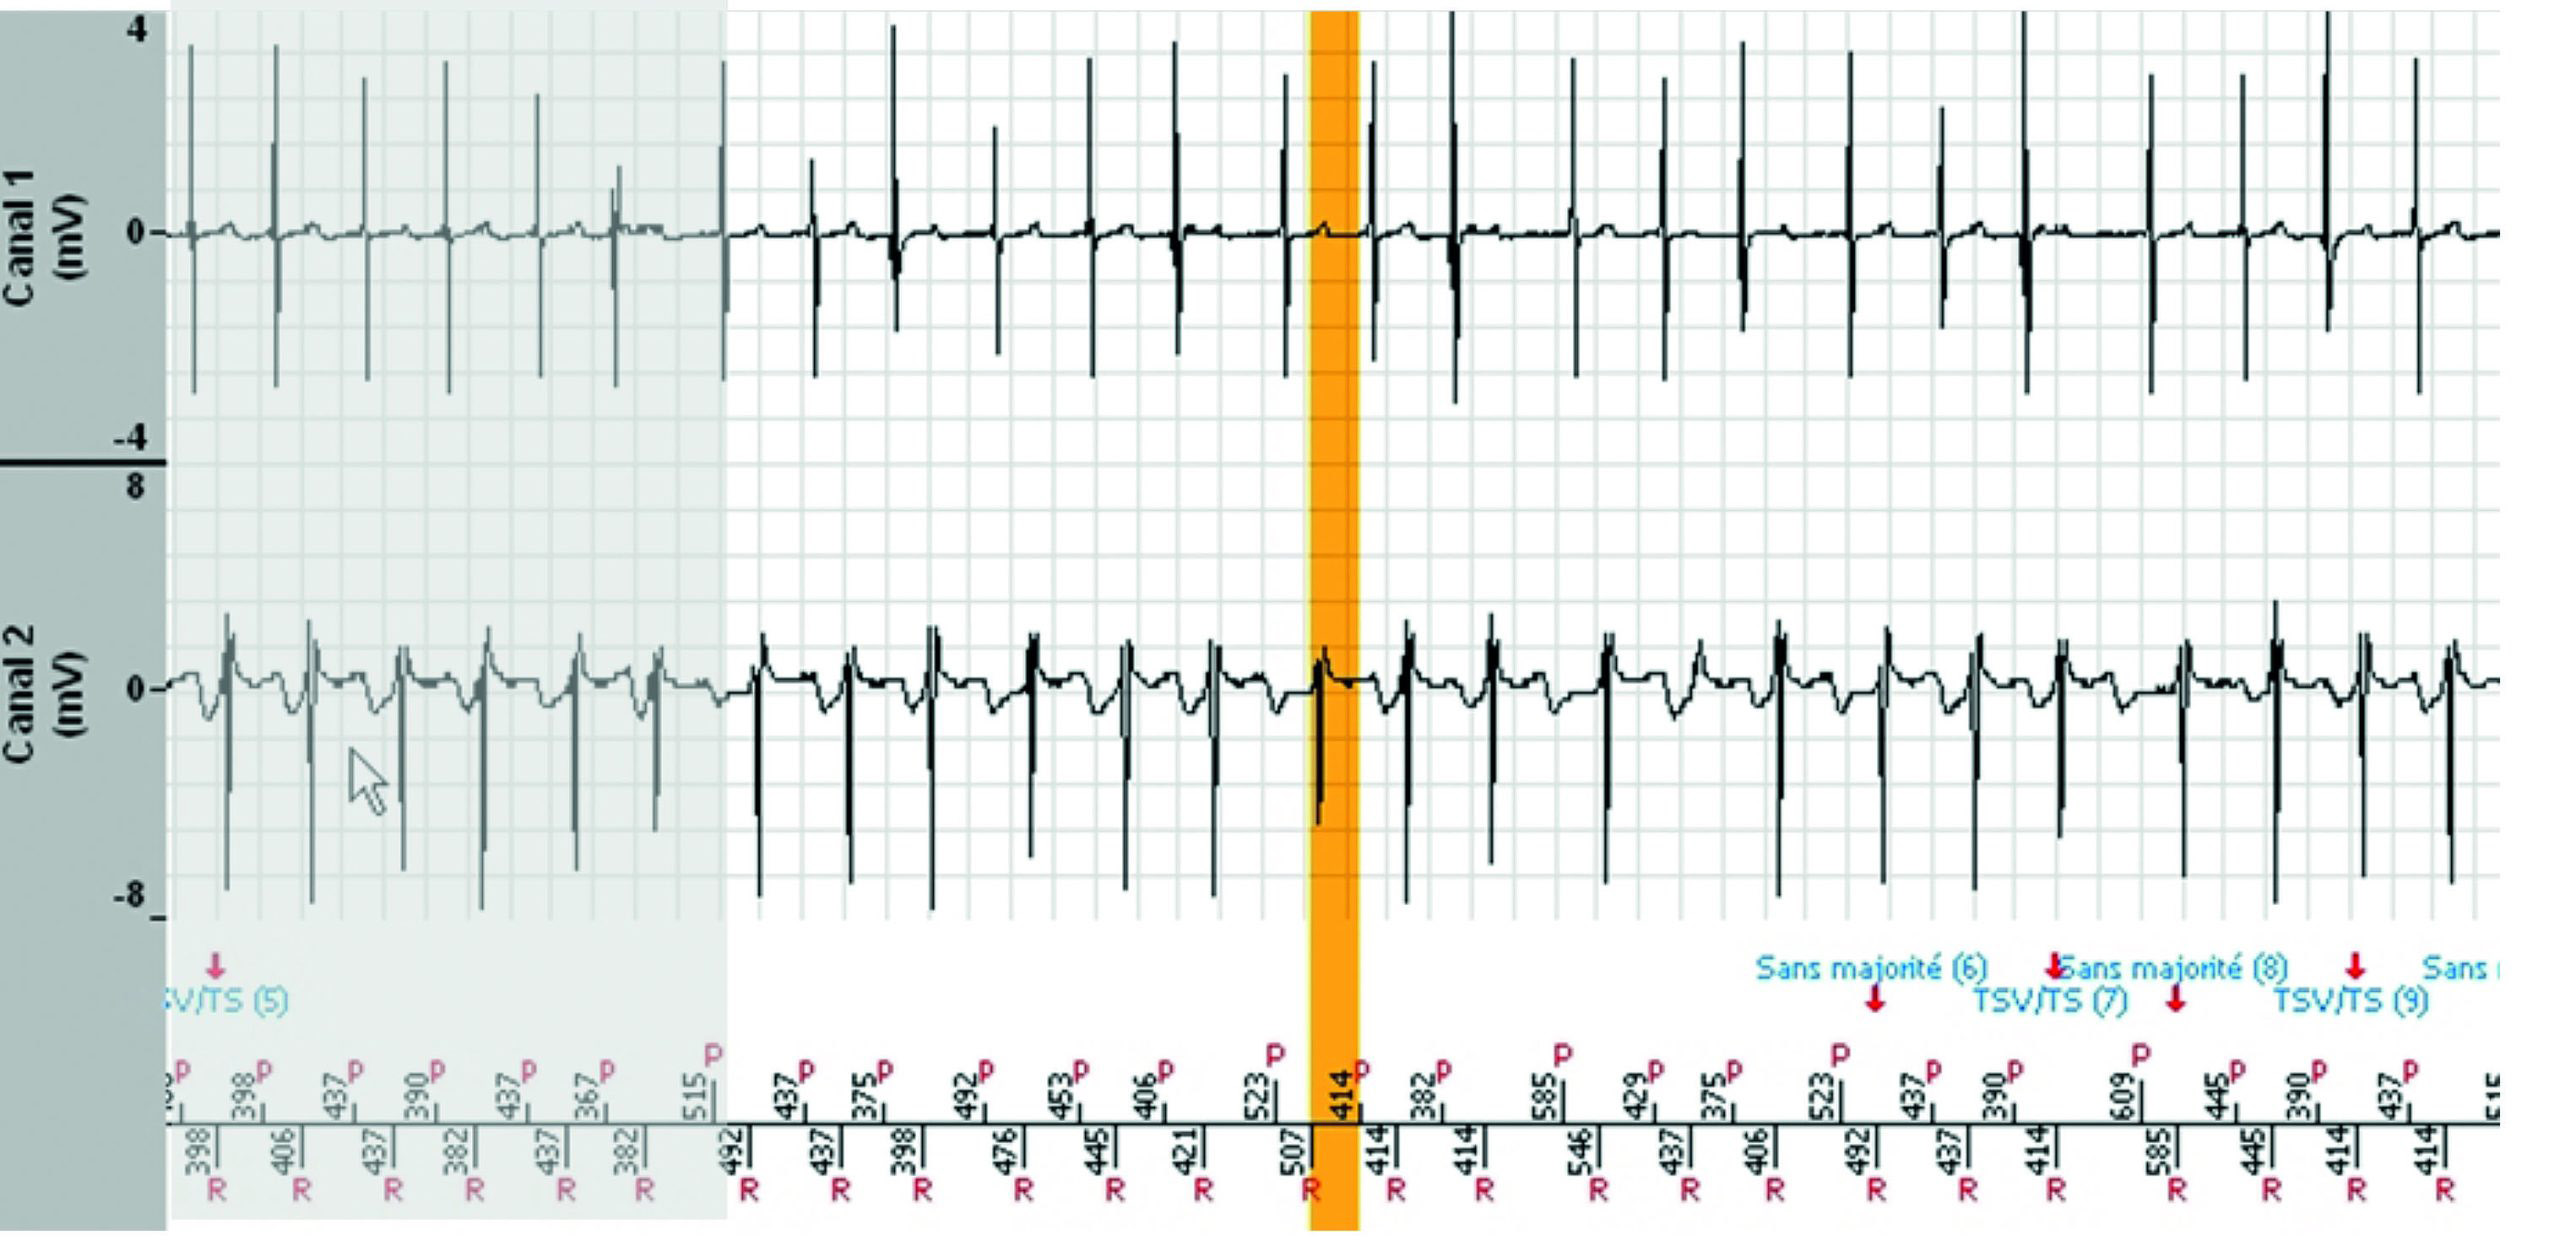

Tachogramme

EGM

Les zones ombragées sont les portions de l'EGM qui sont les répétitions de la fin de l'image précédente.

- Le tachogramme démontre des extrasystoles auriculaires et ventriculaires pendant un rythme sinusal conduit.

- La tachycardie est précédée d'un triplet ventriculaire avec une probable conduction rétrograde, suivie d'une déstabilisation immédiate du rythme auriculaire qui initie une tachycardie auriculaire instable et répercutée dans le ventricule, conduisant au diagnostic de TSV. Chaque variation de l'intervalle P'P’ induit la même variation de l'intervalle RR correspondant. La tachycardie est bien contrôlée par l'oreillette.

- Le diagnostic est non majoritaire lorsque le rythme entre ou revient dans la zone lente (non tachycardique) pendant au moins 3 cycles sur 8 (mais moins de 6), puis redevient instable avec un diagnostic de TSV jusqu'à la fin de l'épisode.

- Aucune thérapie n'a été délivrée.